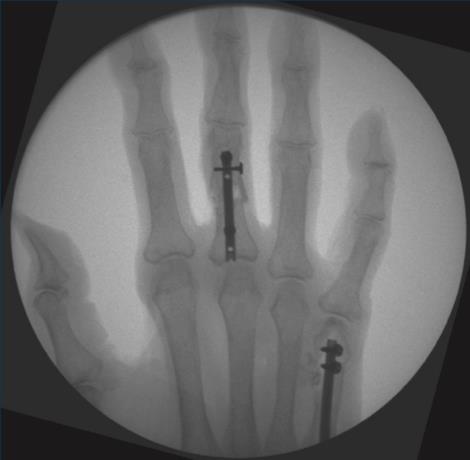

• advance the 2.0mm stop drill through the selected proximal slot, drilling through the near cortex until the mechanical stop reaches the drill guide

• measure screw length with the 1.4mm drill, stopping before the far cortex

• insert the selected 1.8mm locking compression screw unicortically

• confirm final reduction and implant position using fluoroscopy

• repeat the drilling, sizing, screw insertion, and fluoroscopic confirmation steps for the distal screw, taking note of the chosen hand nail length and the drill guide etched sizes